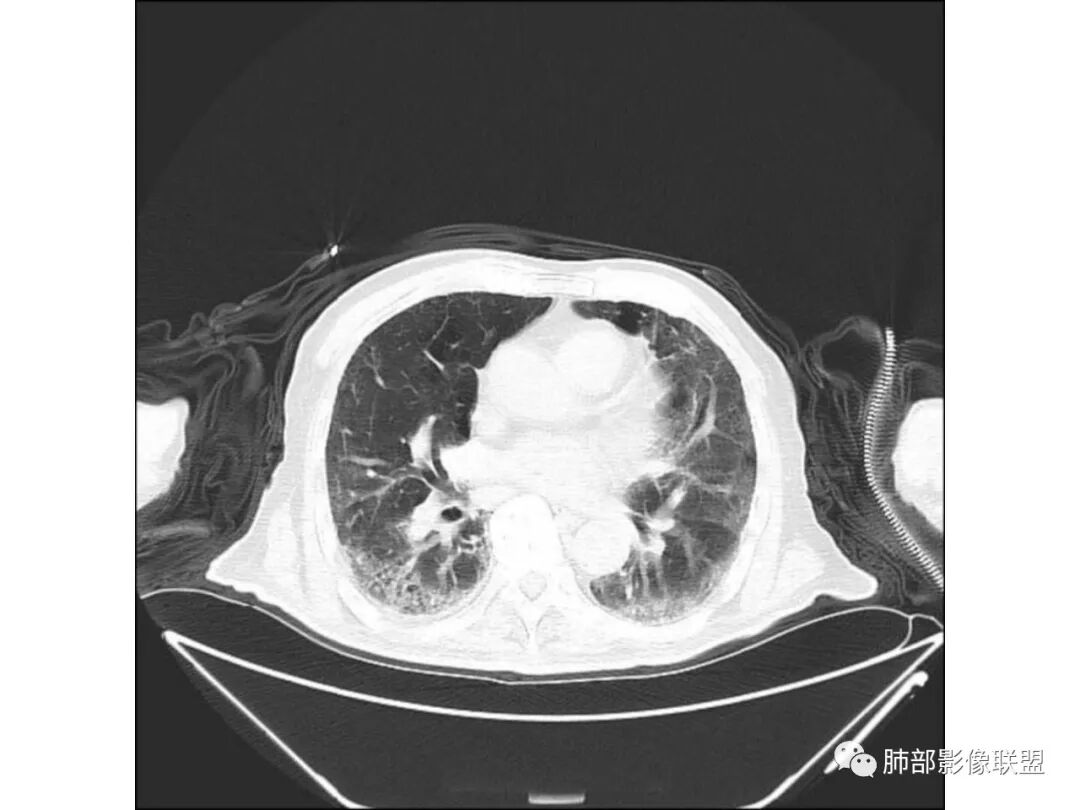

有肺气肿背景,纵隔淋巴结钙化,肺部有纤维化,右肺大片实变,内有融合空洞,未见液平,支气管远端有扩张,部分近段狭窄截断,病灶周边树芽不明显,考虑结核可能大,鉴别腺癌,多为假大空,少有空洞,支气管远端少有扩张所以不符合,肺部感染,多有空洞液平,所以不符合。

老年男性,糖尿病病史,咳嗽咳痰10余天入院。右上肺实变,见支气管充气征,部分支气管扩张,虫蚀样空洞,无壁空洞内壁光滑,实变病灶内见粘液成分,右上肺体积稍缩小,结核和肺炎性肺癌的鉴别,结核可能大,合并间质性肺病。

老年男性,右上肺大片实变,内见支气管充气征,支气管通畅,见多发蜂窝状改变,双肺肺气肿,双肺胸膜下间质性改变。结合病史,咳嗽,糖尿病史,考虑感染,结核可能。鉴别肺炎型肺癌,肺克;建议增强,支气管镜检查

老年男性,咳嗽、气喘十余天。2型糖尿病10年。胸部CT:右肺上叶实变影,见支气管充气征,部分支气管狭窄、虫蚀空洞,空洞内可见磨玻璃影,有囊变,双肺胸膜下磨玻璃影,肺气肿背景。综合考虑良性病变。结核、肺克可能性大。鉴别真菌及恶性。

老年男性,有糖尿病病史,右侧胸廓塌陷,肺容积缩小,右肺上叶片状实变密度影及高密度影,边缘模糊,内可见支气管充气征及多发虫蚀样空洞,考虑结核可能大。肝脏只有一层,看上去正常

老年男性,糖尿病患者。右肺病变,病灶区多发树芽、管状透亮区,考虑为扩张支气管,说明为支气管源性病变。结核?真菌?肺癌?病灶区多发空洞,空洞内坏死不太彻底,树芽征跟增殖结节不明显,结核先不考虑。病灶区晕征不太明显,边界相对清楚,小叶间隔增厚~似呈结节状改变,支气管枯树枝征。最后,肺癌首先考虑,粘液腺癌?鉴别曲霉菌